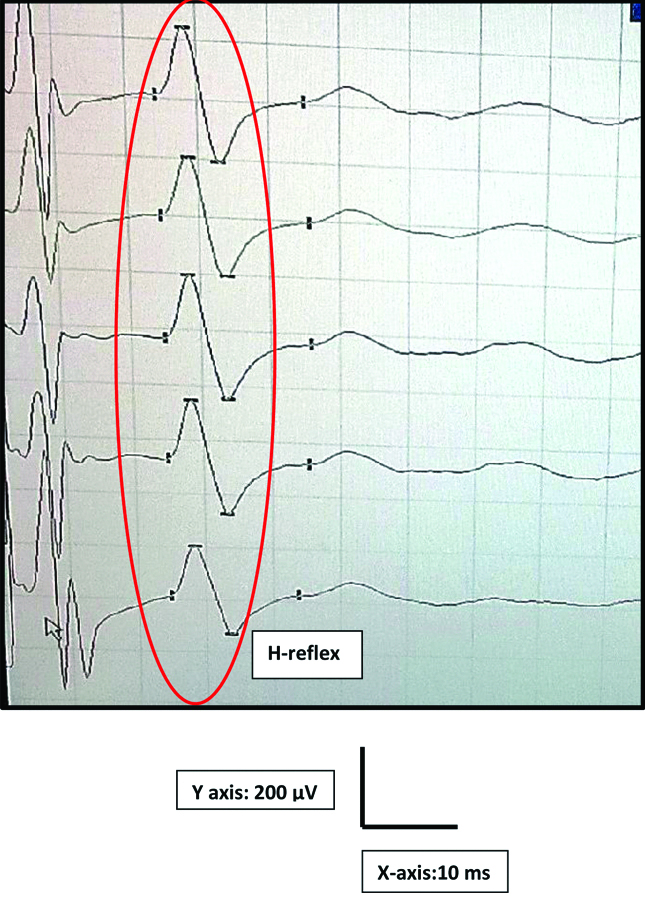

During early follicular phase, the participants were tested in the electrophysiology lab at 22±3°C. With participant in supine posture, the palm was cleaned with spirit to reduce the impedance. In the extended position of the participant dominant hand, the active electrode was placed on APB muscle belly. The reference electrode and the ground electrode were fixed on the thumb and below the elbow respectively [Table/Fig-1]. The participant was asked to abduct the thumb while stimulating the median nerve near the wrist with the intensity of two to five milliampere (mA) for a duration of one ms. The H-reflex was recorded using a digitalized nerve conduction/EMG/EP machine [19,20] (Aleron, Recorders Medicare systems, Chandigarh, India) as shown in [Table/Fig-2].

A typical APB H-reflex recording in RMS machine.